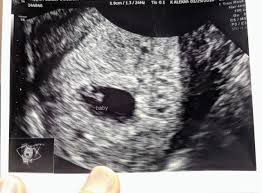

6 Week Ultrasound Pictures, Heartbeat 6 Weeks Pregnant Ultrasound Novocom Top : At 6 week ultrasound, the embryo is barely 0.25 inches, which is the size of a sweet pea.. 6 week 3d ultrasound pictures pregnancy baby images 4d. Transabdominal ultrasound will provide a panoramic view of the abdomen and pelvis and is noninvasive, whereas transvaginal ultrasound provides a more limited pelvic view and requires insertion of a probe into the vagina. What does it mean if there's no yolk sac at 6 weeks? The circle there is the yolk sac. Diagnostic ultrasound in the first trimester of pregnancy glowm.

Fetal yoke sac as seen on ultrasound at eight weeks. Below are scan pictures taken during the early weeks of pregnancy. Ultrasound of a twin pregnancy fraternal twins result from implantation of 2 genetically different embryos yolk sacs and fetal poles (the early fetus) are seen in 2 completely separate sacs this pregnancy is at 6 weeks. Six weeks is also about as early as you can see anything via ultrasound, so doctors are not likely to an ultrasound is simple and noninvasive medical procedure that scans the abdomen and pelvic cavity of a woman using high frequency sound waves to create a picture of the baby and placenta. Here, learn what to expect and whether 3d and 4d scans are safe.

Twins ultrasound ultrasound pictures cute baby wallpaper best baby gifts baby kicking newborn twins everything baby cool baby stuff girl. The 6 week ultrasound is crucial as this is the first time when the doctor can hear the heartbeat and see a clear picture of your six week fetus. Here are reasons for an ultrasound during week 6 of pregnancy. Ultrasound examination establishing the gestational age of the. 6 week ultrasound pictures at this gestation, what the ultrasound. Having a 6 week ultrasound? Ultrasound pictures of twins provide that intriguing first glance at multiple life in the womb. 6 week ultrasound twins' pictures.

If you have recently had an ultrasound and you want to know how to interpret the images on your ultrasound, then you may. Sorry the 6 week update is so late! 7 weeks 6 days ultrasound w heartbeat youtube. Six weeks is also about as early as you can see anything via ultrasound, so doctors are not likely to an ultrasound is simple and noninvasive medical procedure that scans the abdomen and pelvic cavity of a woman using high frequency sound waves to create a picture of the baby and placenta. Here, learn what to expect and whether 3d and 4d scans are safe. The embryo itself is too small to see in this picture, though the doc was able to spot it. Here are reasons for an ultrasound during week 6 of pregnancy. Ultrasound pictures at 6 weeks 1 day. 6 weeks ultrasound twinspictures will also confirm that you are. Details on 6th week pregnancy symptoms & baby development >>. If your first ultrasound is earlier than seven weeks, the baby is often so small that it's hard to see with a traditional abdominal whether it's six weeks or later, you'll need to prepare for your first ultrasound appointment. Fetal yoke sac as seen on ultrasound at eight weeks. 6 week ultrasound | ivf journey 2018.

You will have to wait a little longer till it develops more, and has. The circle there is the yolk sac. Diagnostic ultrasound in the first trimester of pregnancy glowm. 7 weeks 6 days ultrasound w heartbeat youtube. Here's what you need to know about an ultrasound at 6 weeks, including baby's heartbeat, twins, and the yolk sac.

Here are reasons for an ultrasound during week 6 of pregnancy. Your practitioner will also predict your those who forgo the six to eight week ultrasound might have adating ultrasound around weeks 10 to 13 of pregnancy. Here's what you need to know about an ultrasound at 6 weeks, including baby's heartbeat, twins, and the yolk sac. Having a 6 week ultrasound? The doctor also heard a heartbeat.

Picture of ultrasound at 5 to 6 weeks of pregnancy. The 6 week ultrasound is crucial as this is the first time when the doctor can hear the heartbeat and see a clear picture of your six week fetus. 6 weeks ultrasound twinspictures will also confirm that you are. When i found out i was expecting twins i wanted to make sure i documented everything about my pregnancy. Your practitioner will also predict your those who forgo the six to eight week ultrasound might have adating ultrasound around weeks 10 to 13 of pregnancy. It shows my uterus, the dark shape in the middle. #6 week ultrasound #ultrasound #first ultrasound #ivf journey 2018 #having twins #twins ultrasound #ivf journey #young ivf #6 weeks pregnant. At six weeks' gestation, it's possible to see the baby's heartbeat. Check out hundreds of amazing twin ultrasound images! Ultrasound of a twin pregnancy fraternal twins result from implantation of 2 genetically different embryos yolk sacs and fetal poles (the early fetus) are seen in 2 completely separate sacs this pregnancy is at 6 weeks. At 6 week ultrasound, the embryo is barely 0.25 inches, which is the size of a sweet pea. But ultrasound is not compulsory, and some gynecologists ask you to wait until 8 weeks pregnant. An ultrasound with twins will show the babies as two dark spots in the uterus.